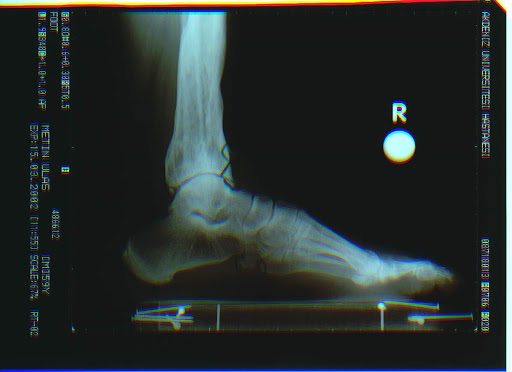

Futbolcu ayağı ( ayak bileği ön kısmı kemik sıkışma)

Ayak bileğinin ön kısmında tibia ve talusta tekrarlayan mikrotravmalar sonucu oluşan traksiyon osteofitleri ayakbileği hareketinin azalmasına ve ağrıya neden olur.

Devamlı ayak bileği ağrısının diğer bir sık nedenidir ( futbocularda % 45, dansçılarda % 59) Cheng and Ferkel,1998 Anterior eklem ağrısı ve ayak bileğinin dorsifleksiyonunun kısıtlanması (kemiksel sürtünme / dejeneratif artrit ) Artroskopik yıkama & spur-yumuşak doku eksizyonu osteoartritin erken evresinde faydalı Tol et al., 2001 Belirgin-ilerlemiş osteoartritte ancak % 29 oranında iyi sonuç elde edilmektedir.Ogilvie-Harris and Sekyi-Otu, 1995